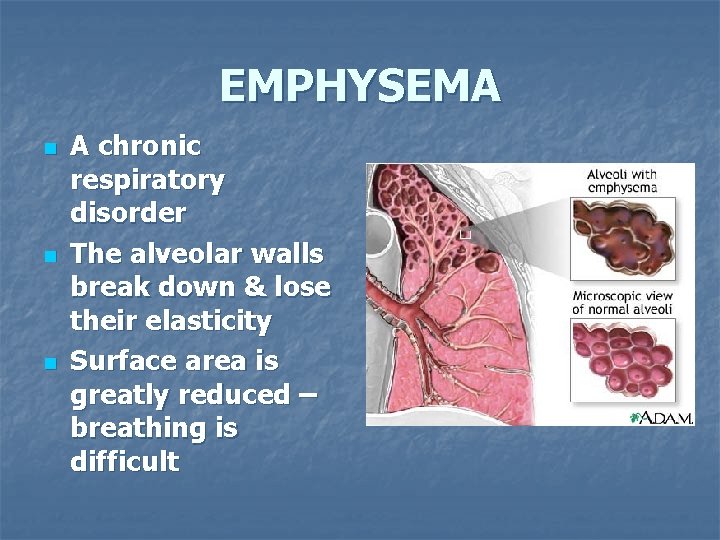

EMPHYSEMA n n n A chronic respiratory disorder The alveolar walls break down & lose their elasticity Surface area is greatly reduced – breathing is difficult